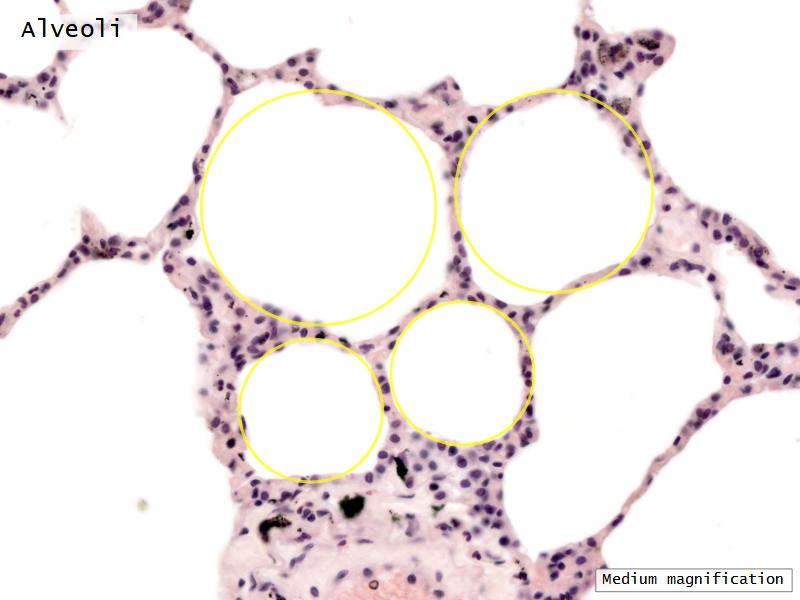

- Alveoli

Lungs